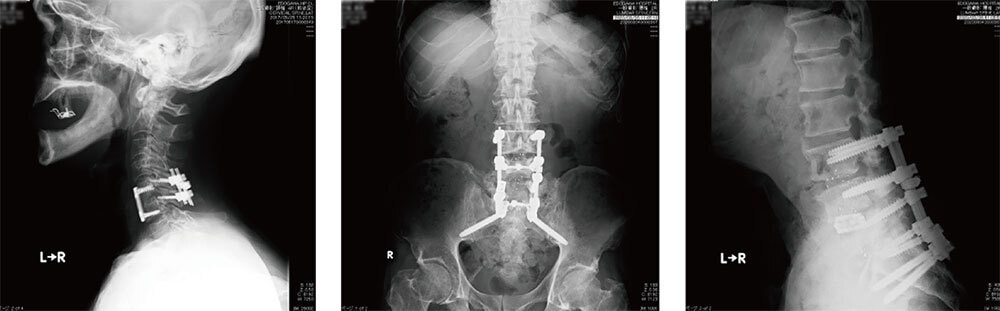

脊椎センター

保存的治療としては主に内服治療・ブロック注射などですが、近年ではヘルニコア椎間板ヘルニア治療(椎間板内酵素注入療法)も行っております。 手術的治療としては、まず最小侵襲手術として腰椎椎間板ヘルニア・腰部脊柱管狭窄症に対して脊椎内視鏡下手術技術認定医を有した医師が内視鏡下ヘルニア摘出術(MED)や内視鏡下椎弓切除術(MEL)、胸腰椎の椎体間固定術(MIS-TLIF 、XLIF)を行っております。

また、圧迫骨折に対して皮膚切開が約5mmのバルーン椎体形成術(BKP)も数多く行っております。その他、頚椎疾患に対する頚椎前方除圧固定術や椎弓形成術など脊椎脊髄疾患に幅広く対応しており、非常にデリケートな組織であることから安全で質の高い医療の提供を心がけております。

手術的治療が必要な患者様がいらっしゃいましたら、まずはお気軽にご紹介いただければと思います。

脊椎内視鏡下手術

頚椎オペ後(左)

腰椎オペ後(中央)

脊椎内視鏡術